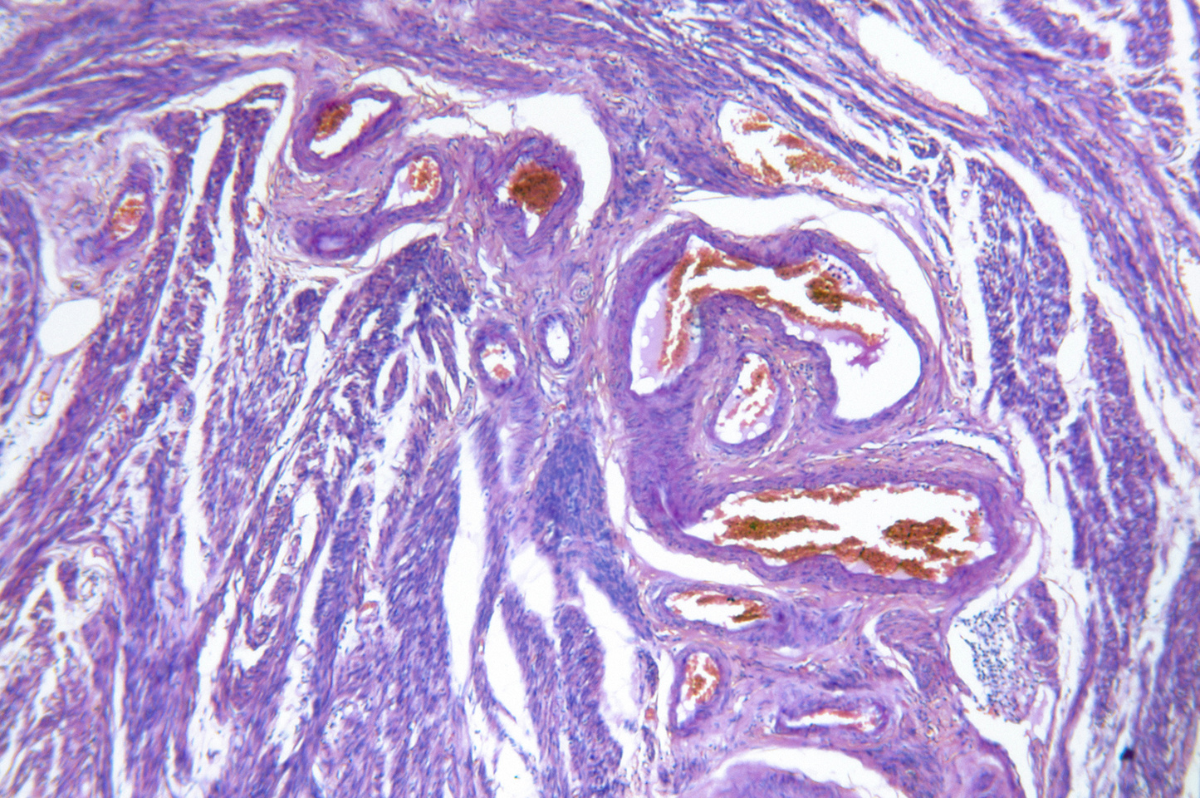

Sentinel Lymph Node Staging in Early-Stage Endometrial Cancer

May 21, 2024Sentinel lymph node (SLN) biopsy is a method used in staging endometrial cancer. It focuses on...

Sentinel lymph node (SLN) biopsy is a method used in staging endometrial cancer. It focuses on...